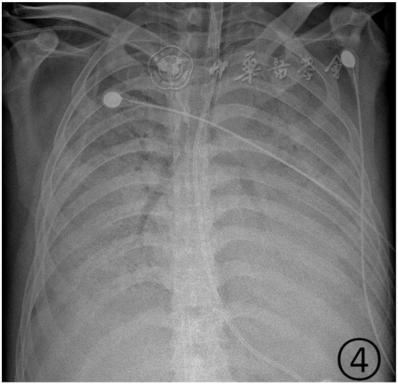

按照国家卫健委发布的新型冠状病毒肺炎试行第六版诊疗方案之中的临床分型,新冠肺炎分为轻型、普通型、重型及危重型。在患者的肺部CT中,轻型者没有比较明显的肺炎改变;普通型者以肺部出现局限性斑片状或很多节段性片状“病灶”为主(图②);重型者双肺可出现较多的白色小斑片“病灶”,部分融合成大片状“病灶”(图③);危重型者会有“白肺”表现(图④)。

▲从上到下依次为普通型、重型及危重型新冠肺炎患者的肺部CT表现(图片来自网络)